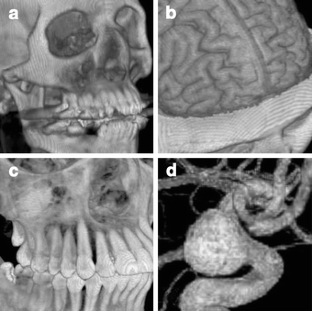

Fig 1.

Fig 2.